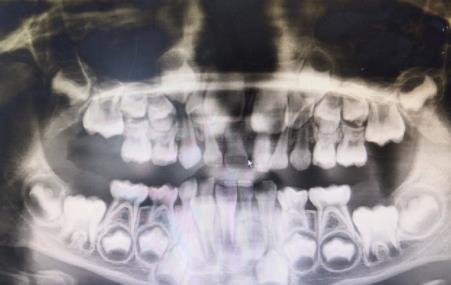

如果是這樣的根尖炎症,影響換牙則建議拔除(箭頭處)